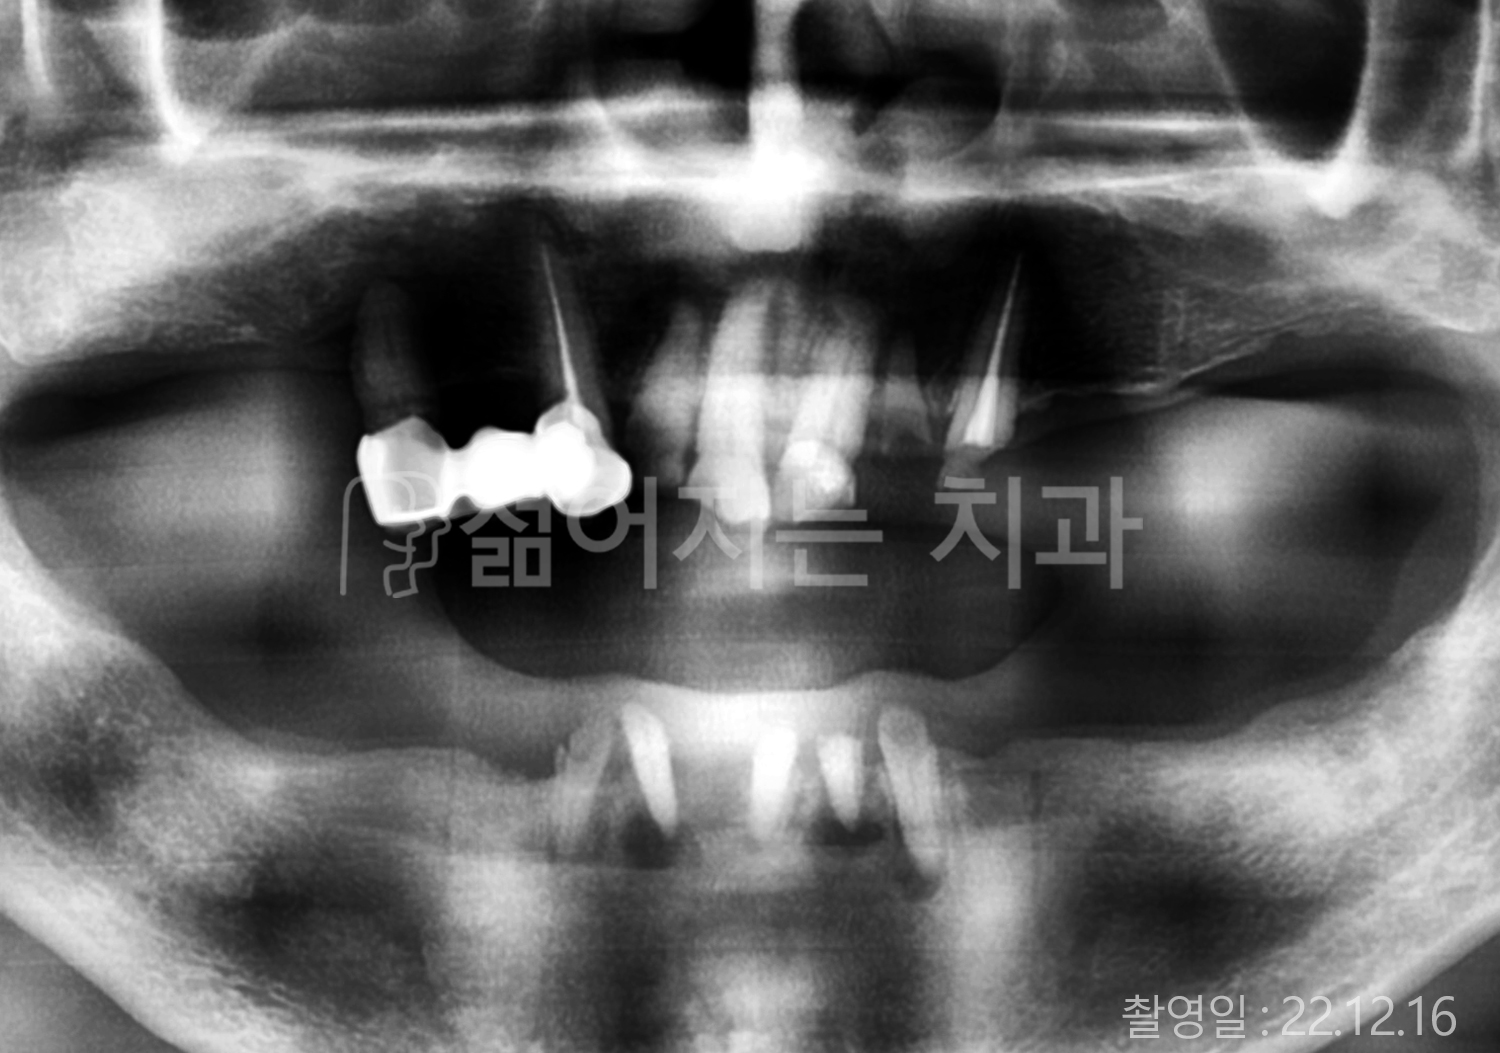

• 50대 전체치아 10개 이상 임플란트